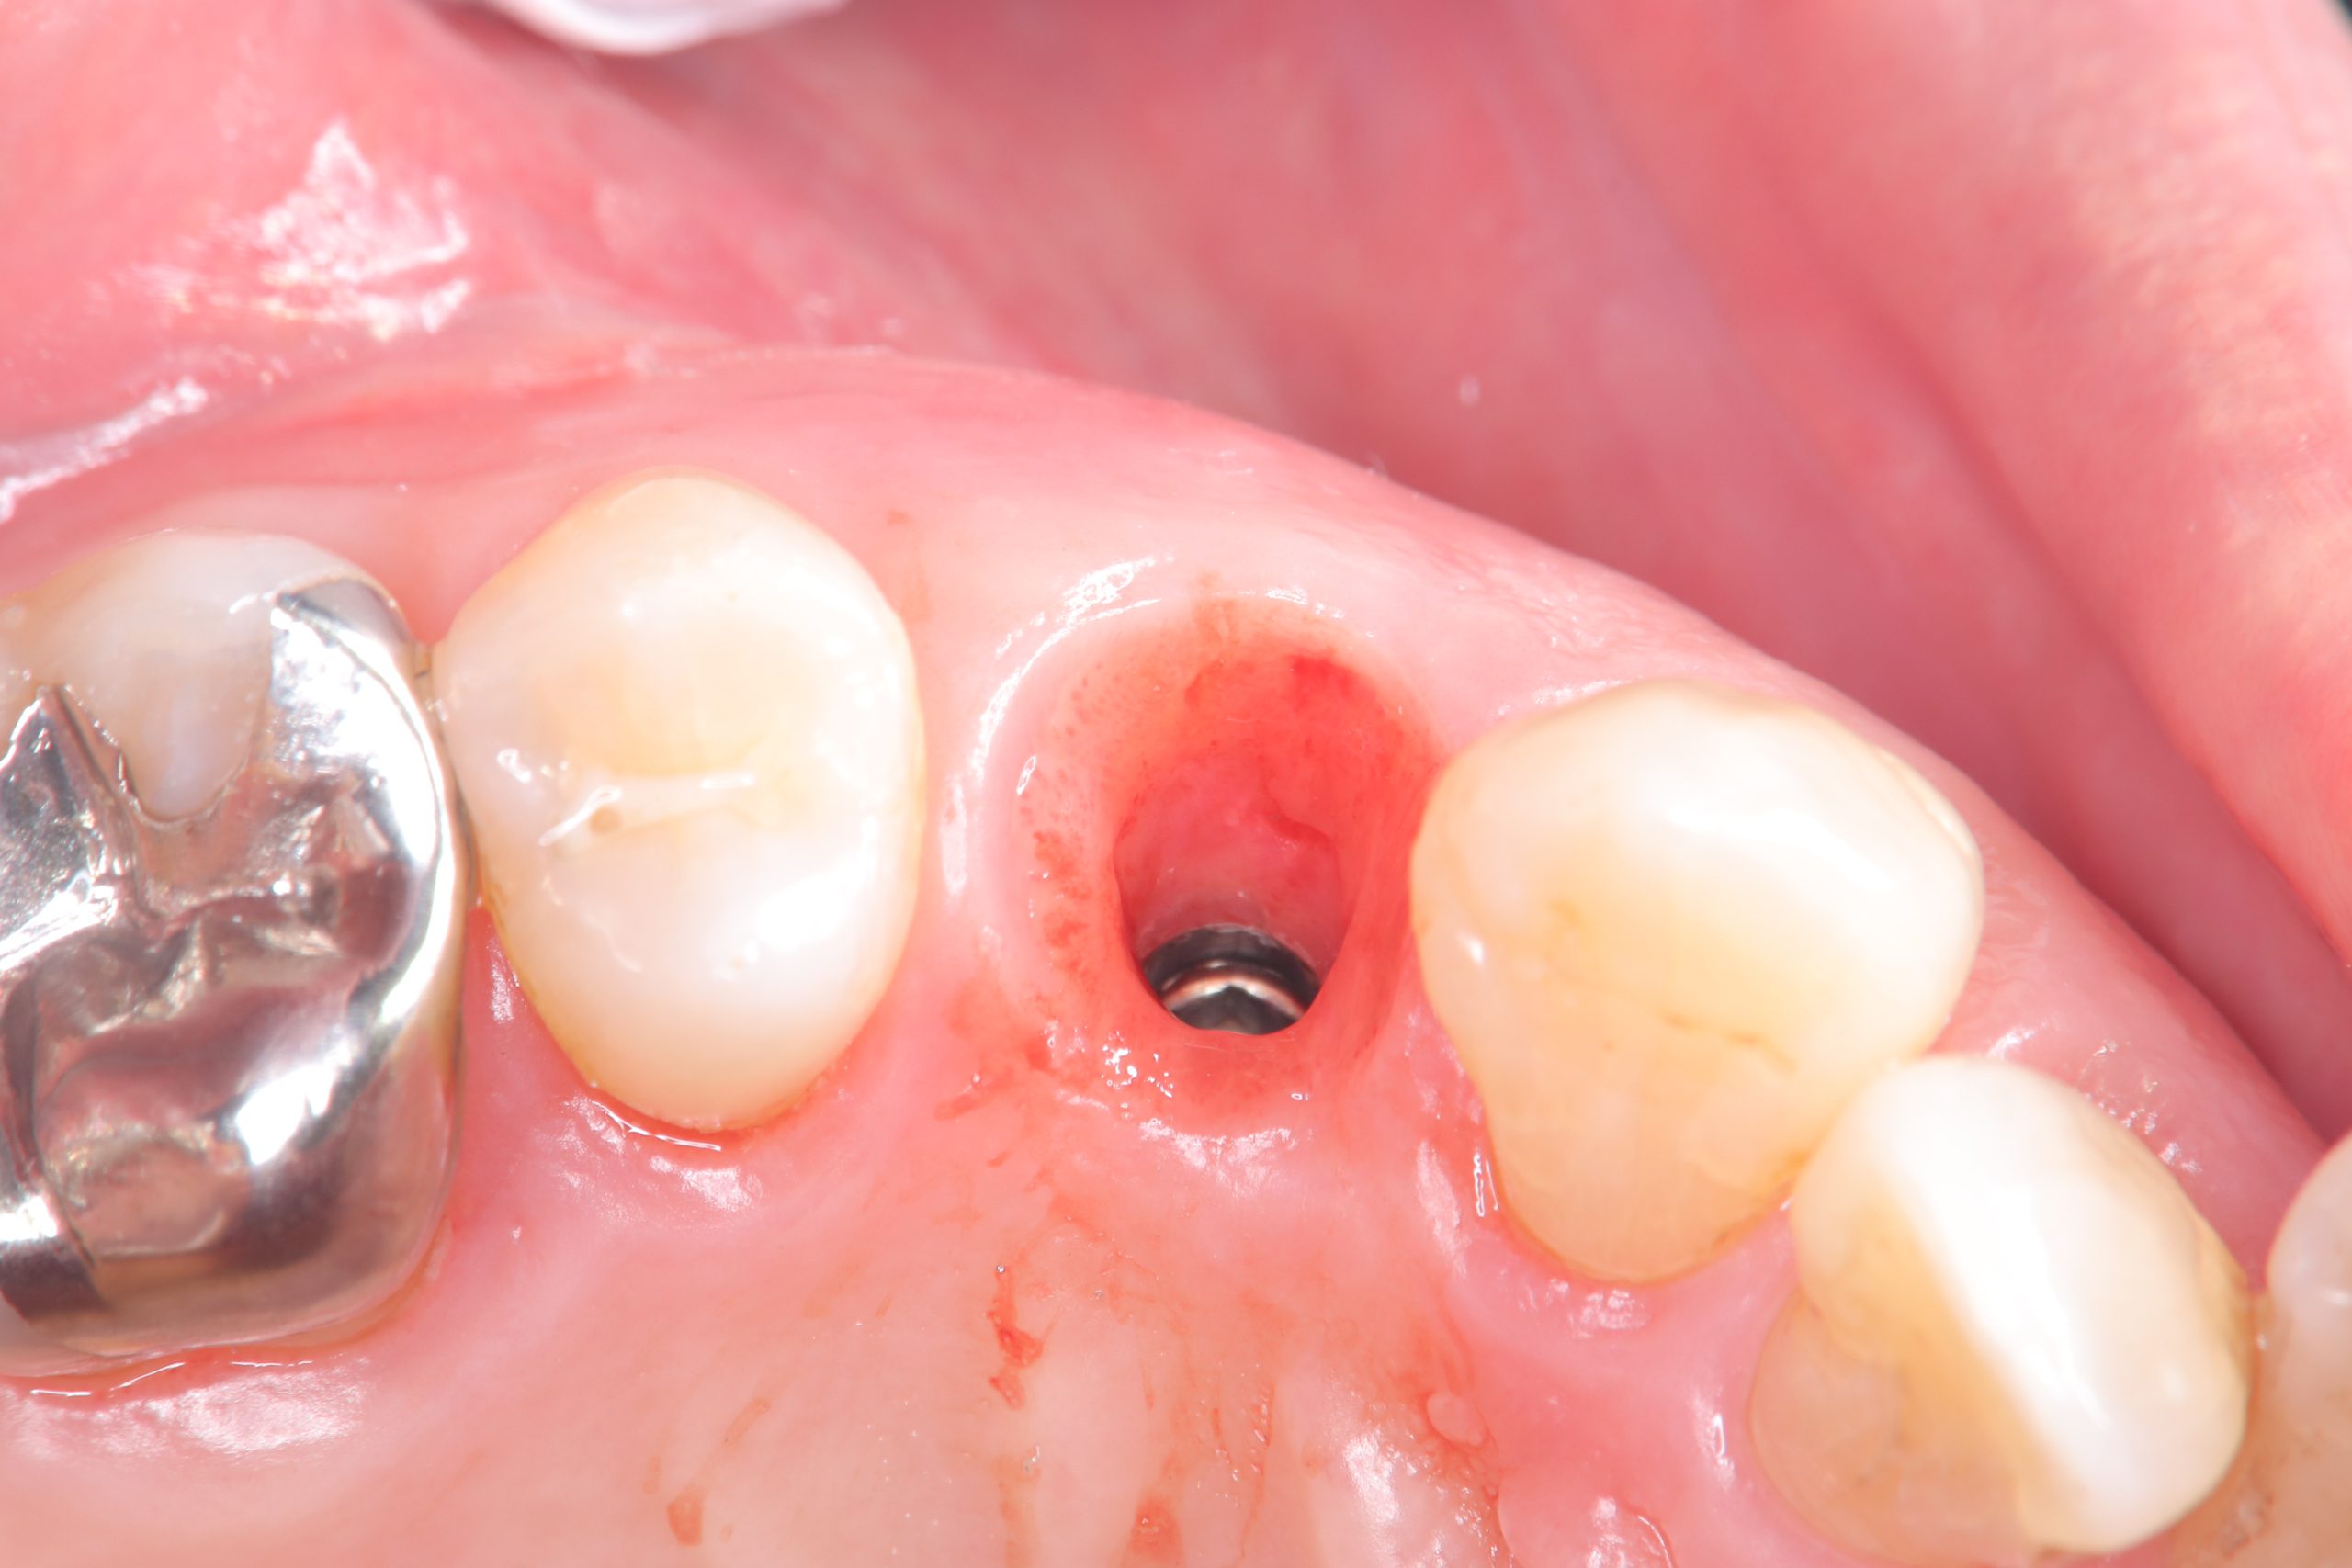

次のお方は、本年4月に抜歯即時、ソケットシールド

セミルーナフラップした方の頬側の骨再生画像確認

ソケットシールドしてるから、吸収なくボリーュミー